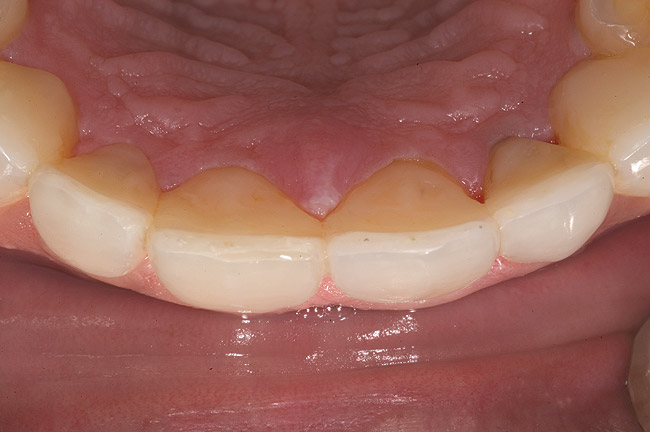

Figure 7  Palatal surface showing loss of form due to enamel dissolution.

Figure 7